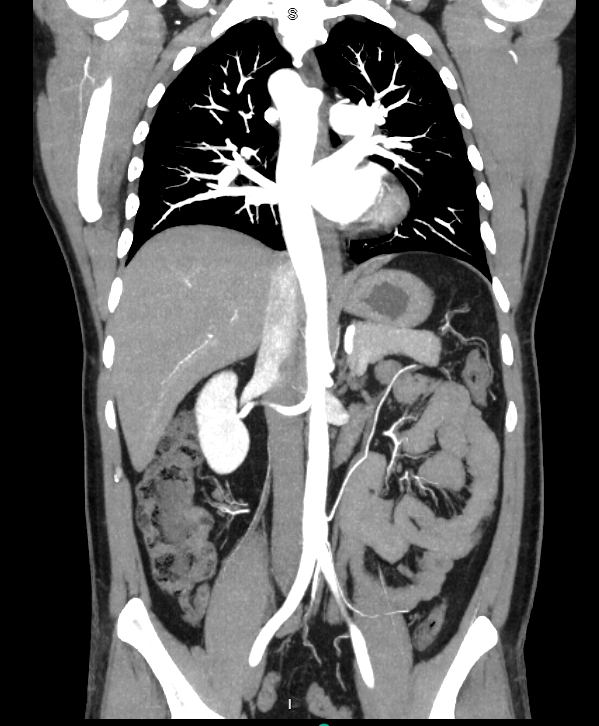

Wrong Turn: Isolated Right-Sided Aortic Arch in the setting of non-ST Elevation Myocardial Infarction

An isolated right-sided aortic arch is a very rare vascular anomaly that usually goes undiagnosed unless symptomatic at birth or during imaging during hospitalization. Here, we present a relatively young patient with a non-ST elevation myocardial infarction (NSTEMI) that was found incidentally to have a right-sided aortic arch.

A 40-year-old male with a past medical history of hypertension, smoking, previous myocardial infarction for which no percutaneous coronary intervention (PCI) was done who presented to the emergency room with left sided chest pain. Initial electrocardiogram (ECG) revealed normal sinus rhythm and a high sensitivity troponin test on admission at hour 0 was negative. A computed tomography scan with intravenous contrast was done, revealing an incidental isolated right-sided aortic arch and an accessory left renal artery. A repeat troponin 12 hours from the first one revealed a value of 1076. Repeat ECG was done which showed nonspecific T wave changes. The patient was loaded with 300 mg of aspirin, 180 mg of ticagrelor, 60 mg of atorvastatin, 0.4 mg of sublingual nitroglycerin, and started on a heparin drip. Decision was made to admit the patient to the cardiac care unit (CCU) for emergent cardiac catheterization. PCI was done on the 15th hour which revealed a 95% stenosis of the distal left circumflex artery and a 70% stenosis of the distal left anterior descending coronary arteries. Angioplasty of the left distal circumflex was performed and a drug-eluting stent was placed with 0% residual stenosis post intervention. Post catheterization, troponins peaked at 1455 at hour 19 and then decreased, with the next value at 898 at the 27th hour. The patient was managed in the CCU and then discharged with outpatient cardiology follow-up.

Congenital large vessel abnormalities are a rare phenomenon and their mechanical impact on vascular diseases are not well established. Right-sided aortic arches are very rare abnormalities and it is possible that this can accelerate shear stress on the endothelial surfaces of the coronary arteries. More studies are needed to elucidate if extra mechanical shear stress could contribute to accelerated atherosclerosis of arteries. Relatively very young patients who present with acute coronary syndrome can be evaluated for congenital vascular structural abnormalities among other causes.